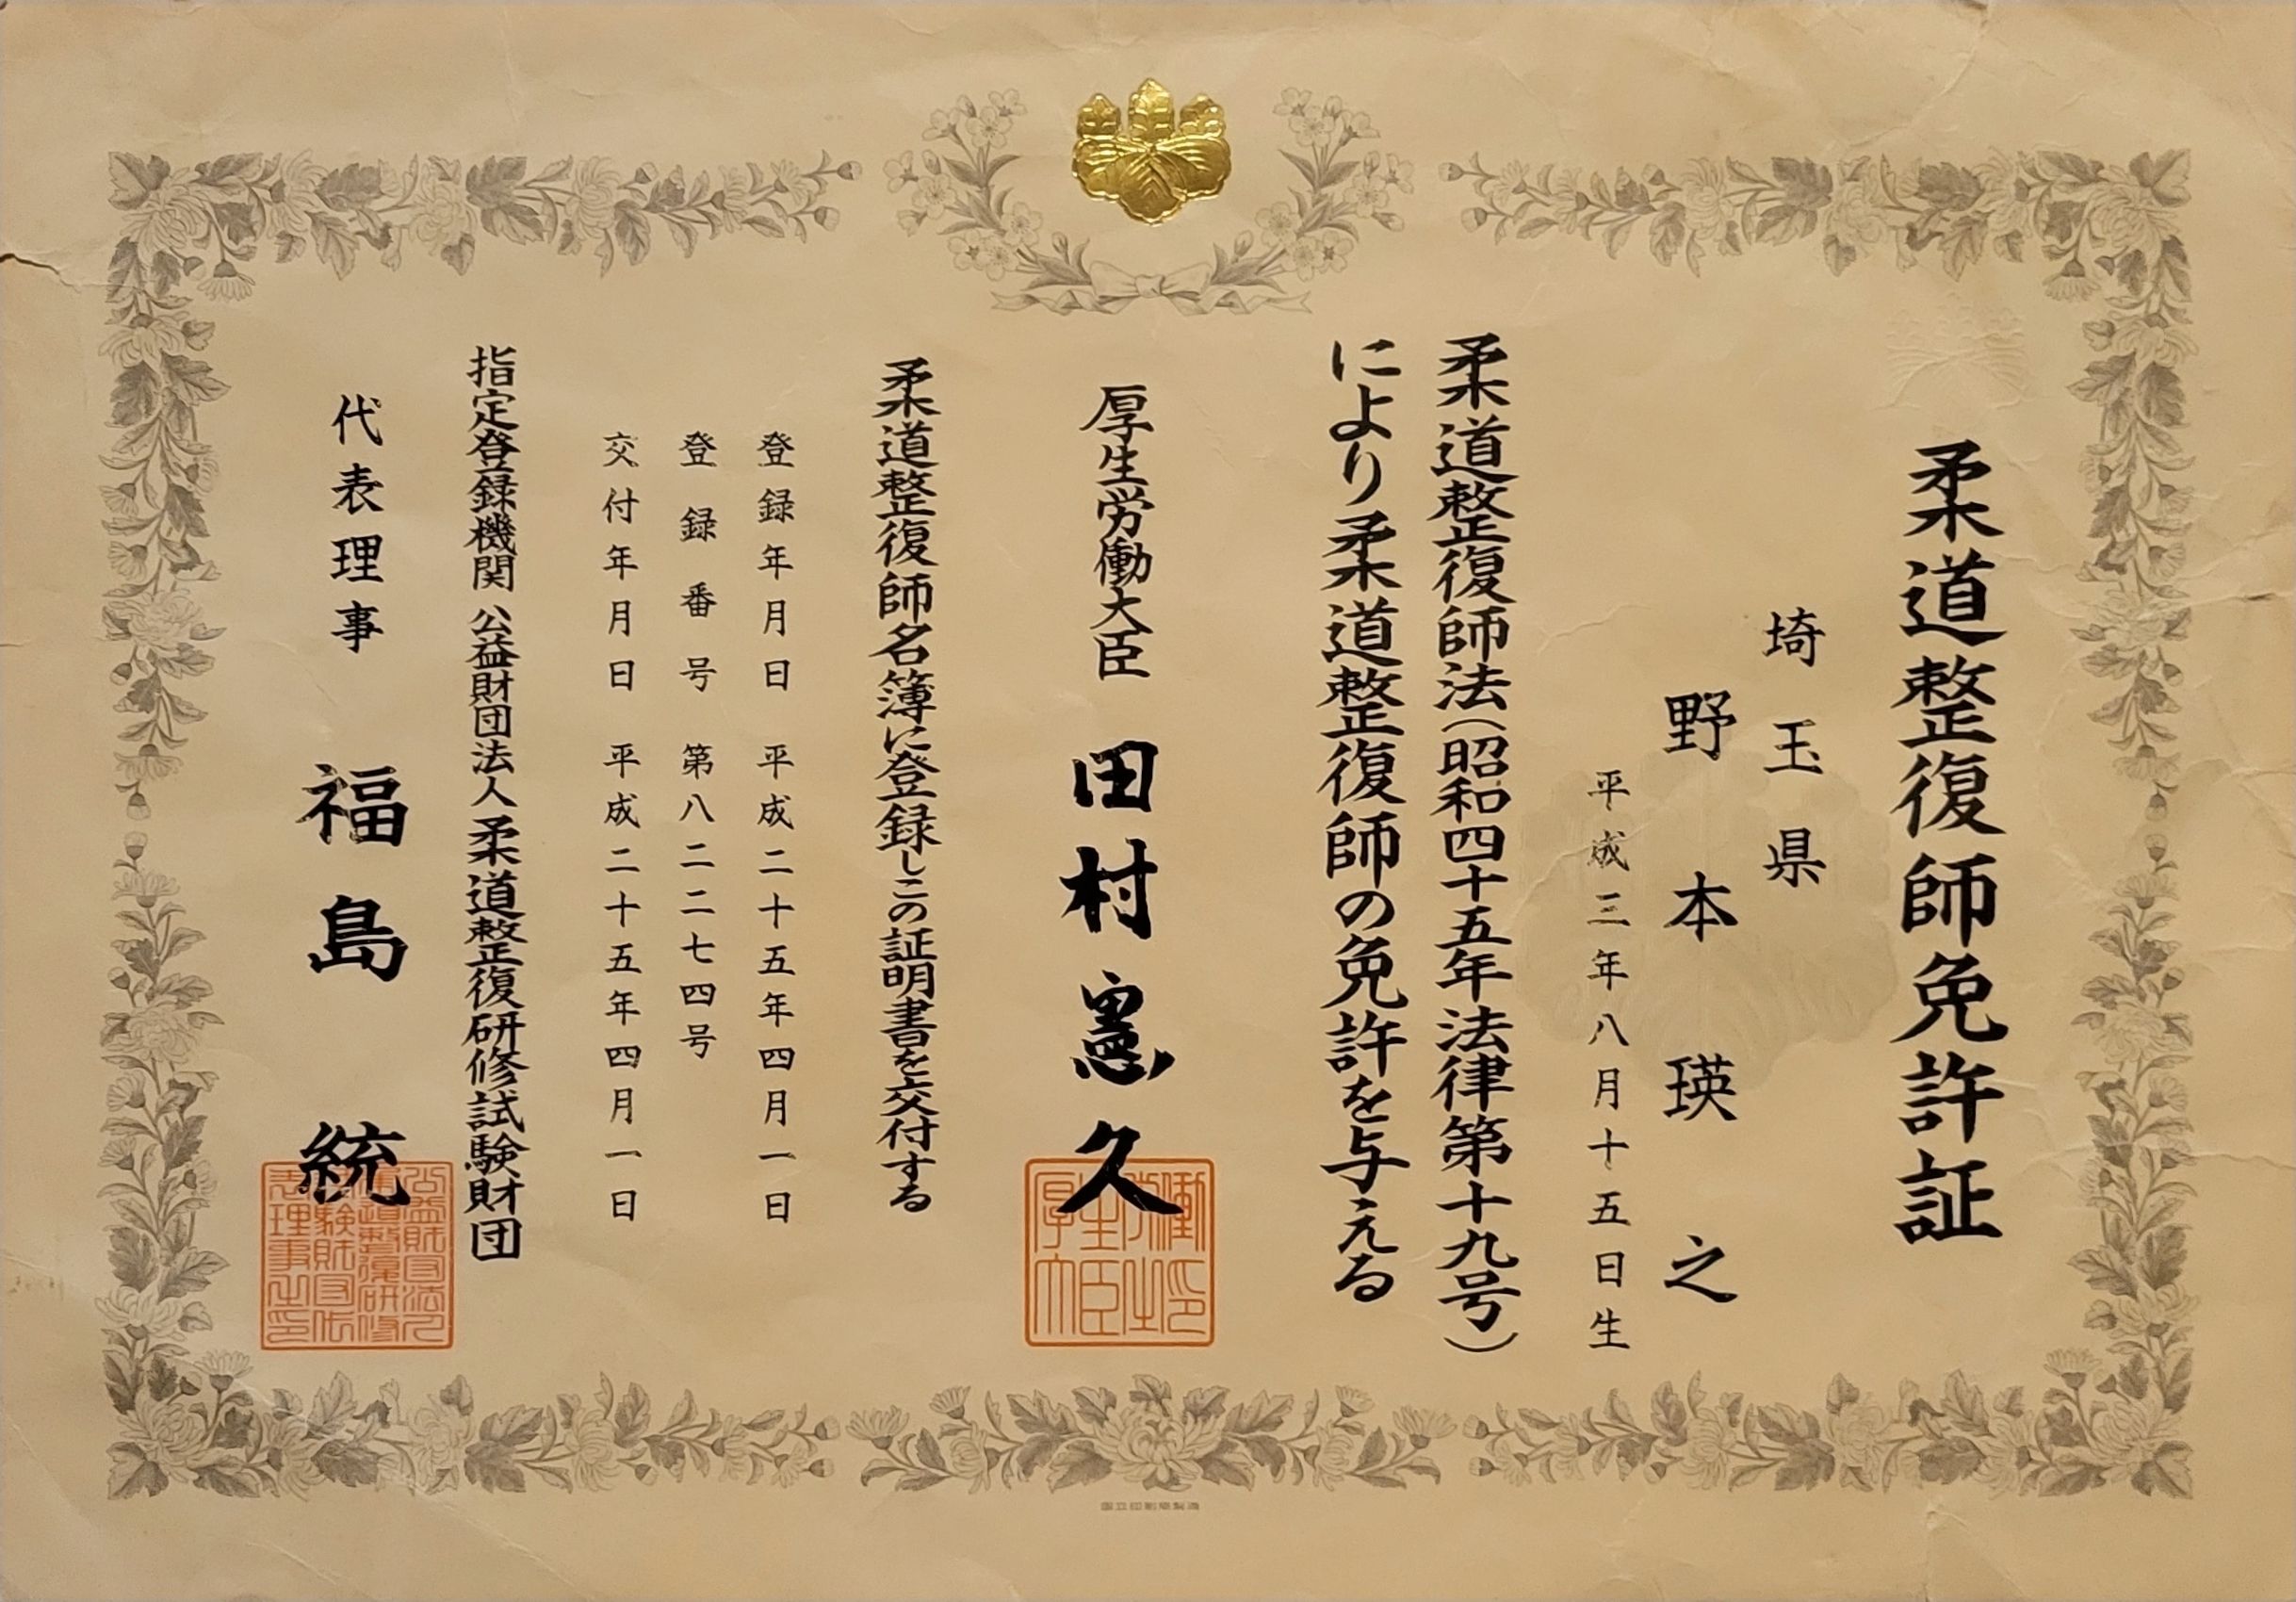

当院は産後のお身体のケアも得意としています💪

お身体にお困りのことがありましたらご相談ください☺️